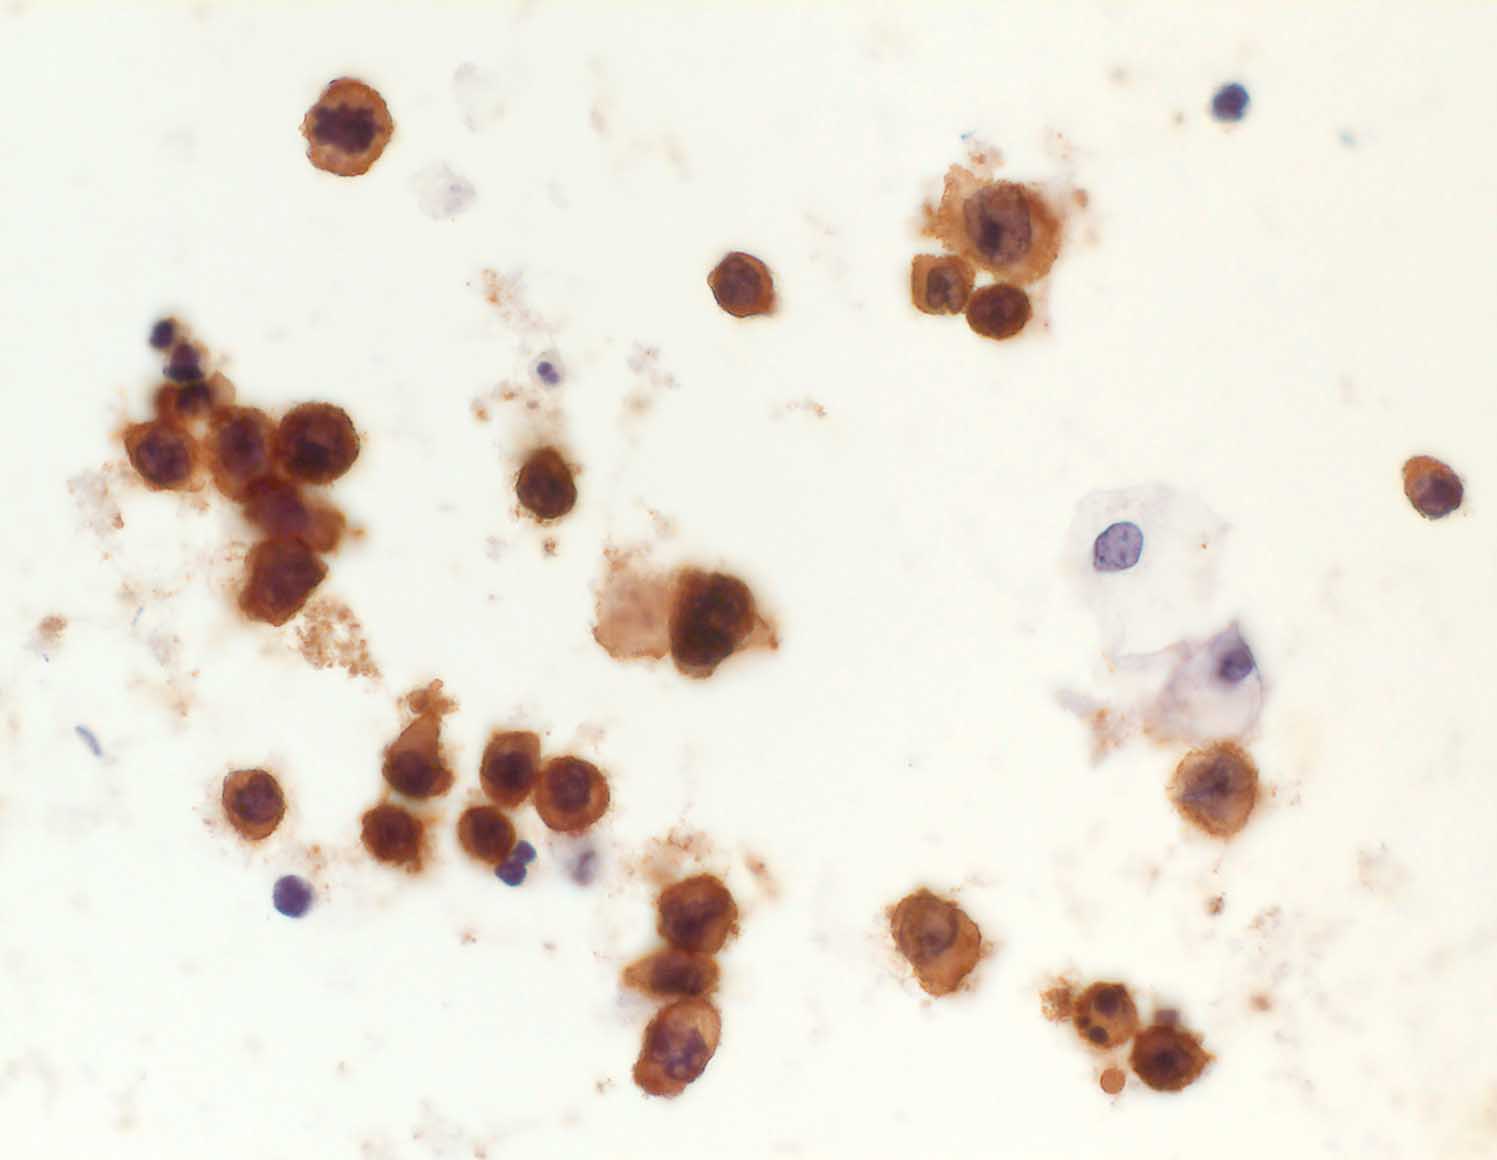

diffuses grosszelliges B-Zelllymphom

Urin: Die atypischen Zellen sind positiv für den Leukozytenmarker CD45.

Sämtliche Tumorzellen sind stark positiv für den Leukozytenmarker LCA, aber negativ für die Epithelmarker Ber-EP4 und Zytokeratin 20. Somit handelt es sich um Zellen eines grosszelligen Non-Hodgkin-Lymphoms, und nicht um Karzinomzellen.

Nieren-Tumor rechts. DD: Urothel-Ca.

Zytologie

Immunhistochemie

CD45 (LCA)

400